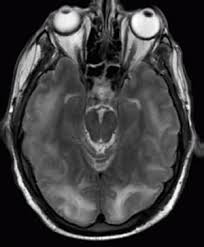

Ct scan without contrast. For a given patient each episode of shunt failure tends to be characterized by similar symptoms 3. Highest incidence of postoperative complications of any neurosurgical procedure.

Normal Pressure Hydrocephalus Wikipedia